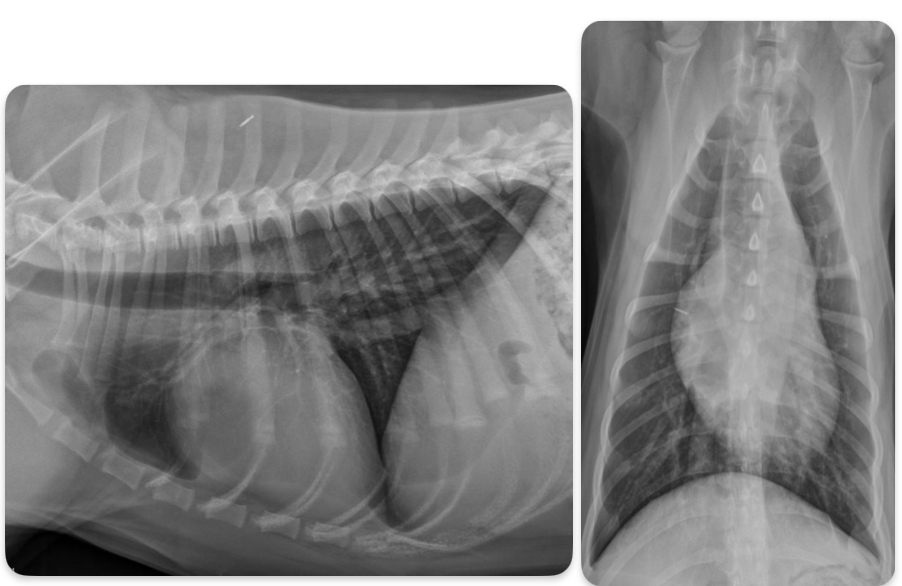

What disease does this dog have

Pulmonic stenosis

Roentgen signs of pulmonic stenosis

-Right heart enlargement (RVE +/- RAE) d/t PRESSURE OVERLOAD

-MPA enlargement

-Normal to small pulmonary vessels (hypoperfusion)

+/- RHF

pathogenesis of pulmonic stenosis

1.Narrow pulmonic valve

2.RV hypertrophies to try and muscle the blood through narrow valve

3.dilation of MPA after the stenotic region

What does the angiocardiography highlight in pulmonic stenosis

-RV hypertrophy

-narrowing pulmonary outflow tract

-post-stenotic dilation of MPA segment